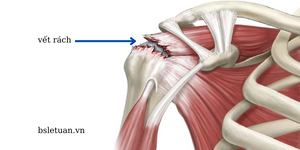

Rách chóp xoay

Chóp xoay là một nhóm gốm bốn cơ quanh khớp vai có tác dụng để chỏm xương cánh tay “quay quanh” ổ chảo. Chấn thương chóp xoay gặp trong các môn thể thao sử dụng tay (quần vợt, cầu lông, bóng bàn, golf …) hoặc khi ngã đập vai xuống nền cứng. Đôi khi là do hiện tượng “vận động khớp vai quá nhiều – overuse” dẫn tới các vi chấn thương ở các sợi gân, tổn thương tích lũy theo thời gian dẫn tới đứt chóp xoay.

Triệu chứng: ban đầu người bệnh thường đau âm ỉ ở khớp vai, thường xuyên làm gián đoạn giấc ngủ vào ban đêm, đặc biệt nặng hơn khi nằm nghiêng về bên vai tổn thương. Ở giai đoạn tiến triển, người bệnh khó đưa tay ra sau lưng kèm theo yếu cánh tay, không thể đưa cánh tay lên cao.

Điều trị: Kết hợp điều trị nội khoa và vật lý trị liệu trong giai đoạn ban đầu khi các triệu chứng nhẹ, khi điều trị nội khoa không cải thiện cần phẫu thuật nội soi khâu chóp xoay.